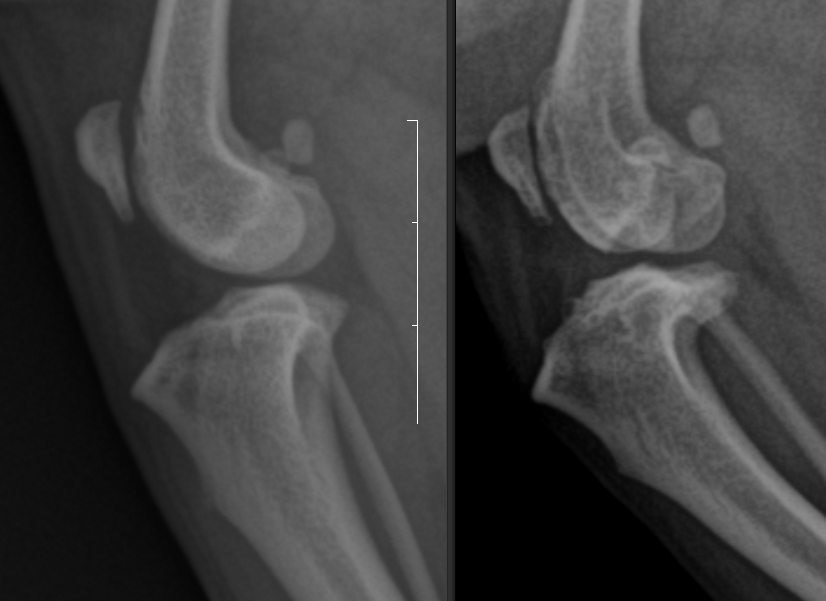

슬개골 탈구는 grade가 낮을때 빨리 하는 게 가장 유리하고 수술하지 않을 때는 복합질환으로 발전한다는 사실을 반드시 명심해야 한다.